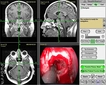

Bu belirtiler malign tümörlerin varlığını gösterebileceği gibi, başka sağlık sorunlarının belirtisi de olabilir. Bu nedenle, belirtilerin ortaya çıkması durumunda bir sağlık uzmanına başvurulması önemlidir. Malign Tümörlerin Tanı YöntemleriMalign tümörlerin tanısı, çeşitli yöntemler kullanılarak konulmaktadır. Bu yöntemler arasında:

Bu tanı yöntemleri, malign tümörlerin varlığını belirlemek ve tümörün türünü, evresini değerlendirmek amacıyla kullanılmaktadır. Erken tanı, tedavi sürecinde büyük bir öneme sahiptir. Malign Tümörlerin Tedavi SeçenekleriMalign tümörlerin tedavisi, tümörün türüne, evresine ve hastanın genel sağlık durumuna bağlı olarak değişiklik göstermektedir. Başlıca tedavi yöntemleri şunlardır: